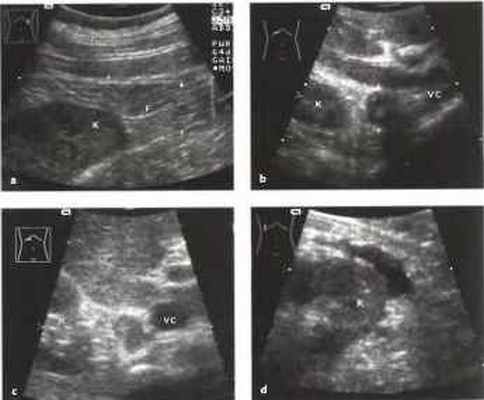

Рис.6. a-d Околопочечное образование, а Околопочечный жир (F). Стрелки: фасция Герота, окружающая околопочечную жировую капсулу, К - почка, b Аденома правого надпочечника (стрелка), выявленная случайно как образование со сложной структурой. Дифференциальный диагноз: феохромоцитома, метастазы, первичная карцинома. Гормональные тесты были отрицательными, с Метастаз бронхиальной карциномы в надпочечник (курсоры), располагающийся между верхним полюсом почки (К) и полой веной (VC). d Околопочечное скопление жидкости, сообщающееся с почкой на перикапсулярном уровне. Дифференциальный диагноз: абсцесс, гематома, уринома.